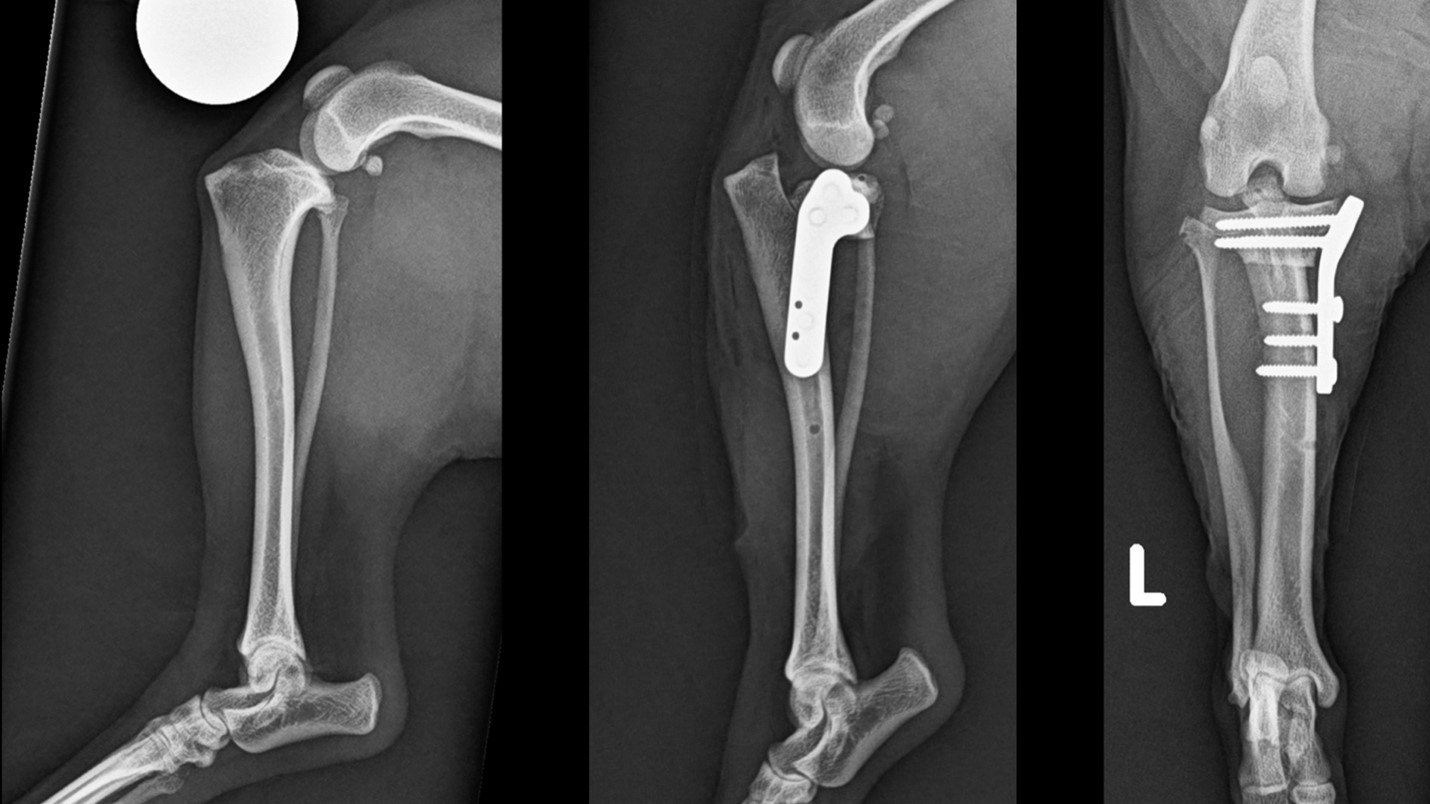

The profession has routinely recommended surgery for medium and large breed dogs for many years, with mounting evidence of the superiority of plateau levelling procedures. Tibial plateau levelling osteotomy (TPLO) is widely performed for large and medium-sized dogs, but less frequently so for small breeds. Despite very limited and quite poor evidence supporting conservative management, non surgical management of small dogs with a rupture cruciate has historically been very common.

This is in spite of the fact that specialized equipment and implants for executing a TPLO on toy breed dogs has been routinely available for over a decade. Fortunately there is now a growing body of published evidence documenting the safety and biomechanical value of this procedure in this cohort. The bottom line is that surgery is a completely realistic prospect these days even for small and toy breed dogs, and really, we should—and we can—recommend surgery over conservative management much more regularly. The latter typically leads to an inferior outcome for these pets, and they deserve better.

An area of growing understanding is in the treatment of these dogs with both cranial cruciate ligament rupture and patella luxation. These are two different but related problems in the stifle. The literature describes a plethora of approaches, and the decision-making process can be very challenging. When should we prioritize one problem versus prioritizing both problems? What techniques should be combined and in what cases should they not? Does the morbidity of correcting a commonly chronic and complex biomechanical issue (patella luxation) alongside the more recent issue (cruciate rupture) make sense in each case?

The rapid evolution of surgical equipment and implants has contributed hugely to rising success rates and increasing complexity of surgical procedures in toy dogs. It is pivotal that the sharing of ideas and practitioner education is prioritized to disseminate these techniques and ensure they are being applied safely and effectively. Selecting the appropriate technique (e.g., TPLO vs lateral suture for cruciate disease) requires an appreciation that historic recommendations have evolved.